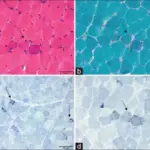

Pleomorphic Adenoma

Pleomorphic adenoma is a benign tumor made up of both epithelial and stromal tissue.

Pleomorphic adenoma is the most common salivary gland tumor.

Pleomorphic adenoma appears as a moving, painless mass that is constrained to the angle of the jaw.

Histologically pleomorphic adenomas have a myxoid component and a stromal component.

Pleomorphic adenoma is associated with the PLAG1 gene mutation.

Treatment of pleomorphic adenoma is surgical resection.

Small islands of tumor that extend through the tumor capsule frequently result in an incomplete resection.

There is a high recurrence rate for excised pleomorphic adenomas.

Rarely the benign pleomorphic adenomas may develop into their malignant counterparts carcinoma-ex pleomorphic.